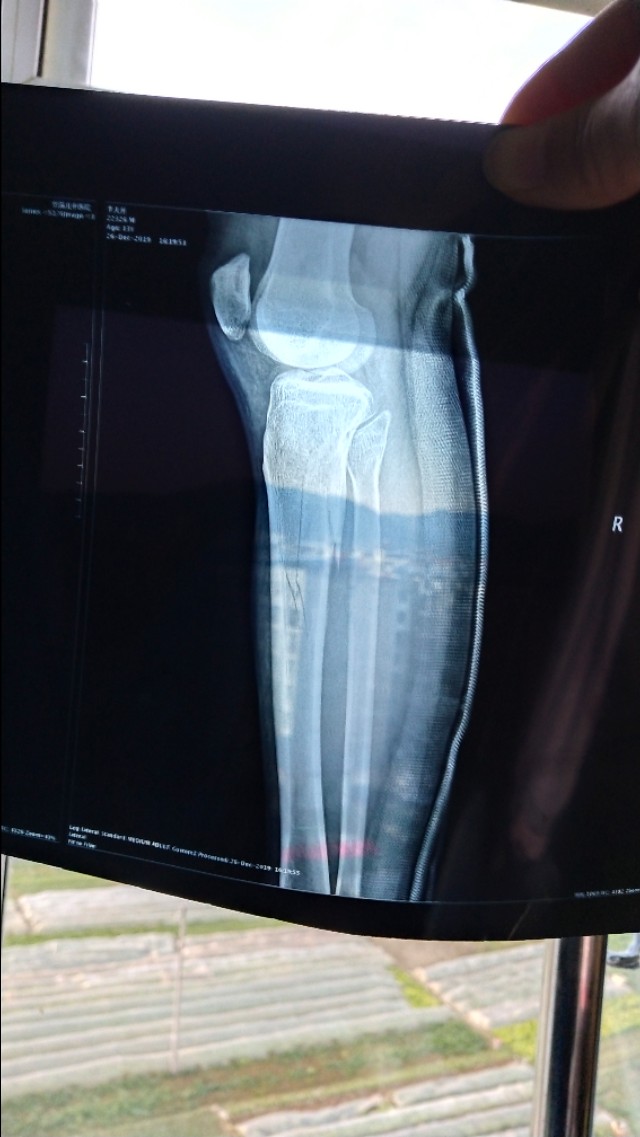

2019年12月19号受伤至今已经150天,是被重物砸伤,拍片检查胫骨平台粉碎性骨折,我也自己老了片子确实裂了好几道口子,医生建议手术治疗,手术目的是固定骨折部位提前解放关节防止后期出现关节粘连。

从车站出来家人陪我去了当地人民医院拍片检查,防止长途颠簸出现严重的二次伤害,好在片子出来后问题不大,医生也说可以保守治疗,回家慢慢修养,定时拍片检查。

后来疫情可控后又去医院拍了两次片子,80天的那次腿部出现了血栓,骨折线稍模糊 开了两盒治疗血栓进口药,140天的时候检查血栓没有了但是有了骨质疏松,骨折线稍模糊。